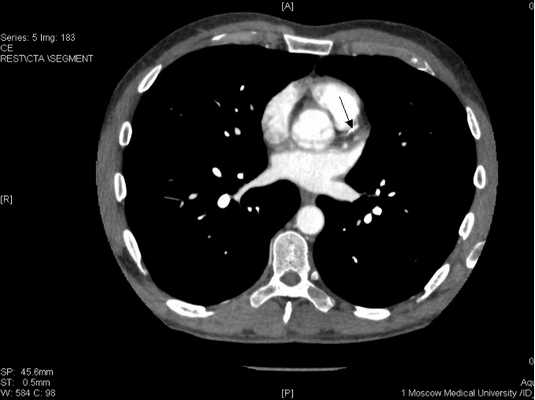

Поскольку от предложенной коронароангиографии пациент вновь отказался, была проведена мультиспиральная компьютерная томография коронарных артерий с контрастированием, которая продемонстрировала протяженный стеноз передней межжелудочковой артерии и окклюзию правой коронарной артерии

Рисунок 11. Стенозирующий атеросклероз коронарных артерий у больного К., 53 лет.

ПМЖВ в проксимальном сегменте имеет кальцинированную протяженную бляшку со стенозированием 50-75% (Указано стрелкой

![ibs11.jpg]()

ПКА в проксимальном сегменте окклюзирована (указано стрелкой), дистальный отдел и ЗМЖВ заполняются контрастным веществом.

![ibs11b.jpg]()